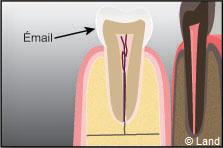

La partie la plus externe de la couronne, l’émail, est composée principalement d’éléments minéraux, ce qui lui confère dureté et solidité.

La dentine est composée d’une trame moins minéralisée, située sous l’émail.

Dans la partie centrale de la couronne se trouve la pulpe innervée et vascularisée. L’intérieur de la pulpe est rempli de vaisseaux sanguins et de nerfs. Ces nerfs donnent la capacité de réagir au chaud, au froid et à la douleur. Les vaisseaux sanguins procurent l’alimentation à la dentine, permettant la réparation de cette dernière lorsque la dent subit un traumatisme.